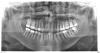

Уважаемые! Подскажите, есть ли воспаление на нижней 7-ке или 8-ке слева? Год ходил с временной пломбой(хорошее качество, не беспокоило) т.к не мог иначе...Пришел долечить, спасти зуб(7-ка). Поковырявшись рач поставила временное заполнение каналов и сказала, что две недели походи, если сильно заболит(в течении первых 4х дней) то удалять(несмотря на то что вобще то год не беспокоило), я спросил -почему? Обяснила воспалением под корнями...Так ли это или развод? Зачем две недели ходить с временным наполнителем(дорого взяли)??? Есть воспаление под зубом по вашему?